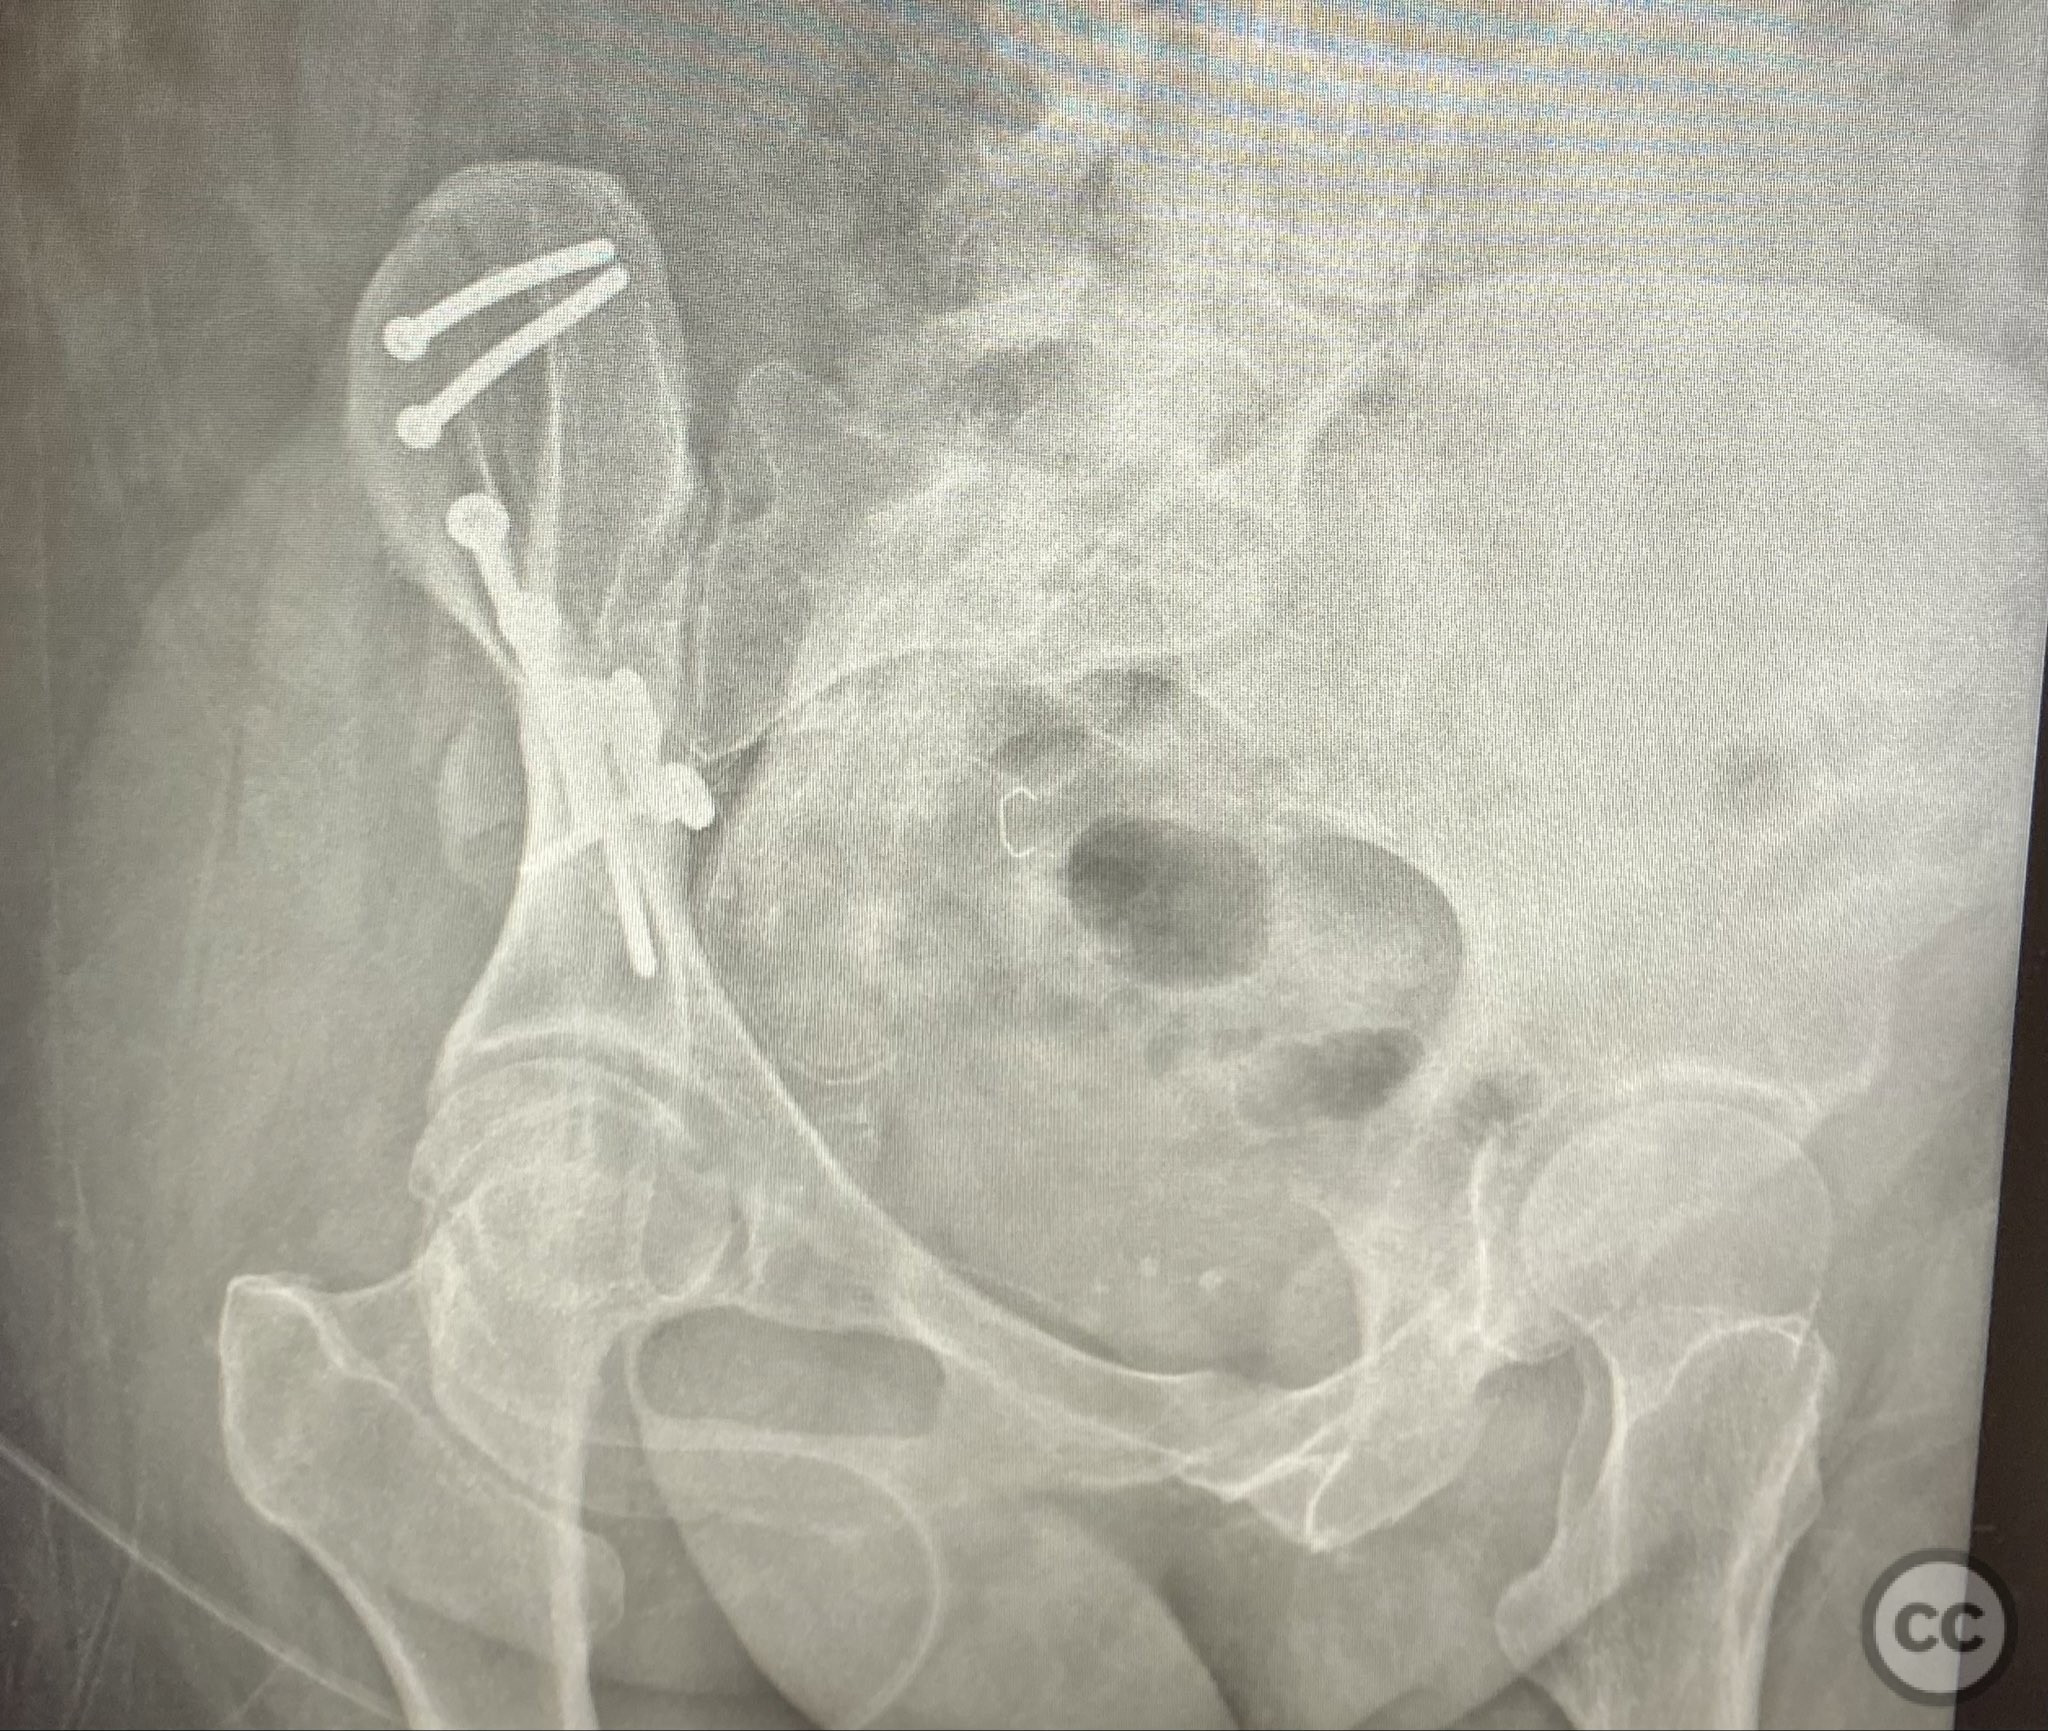

Operative remarks:

The comminuted fragments were mobilized and reduced using pointed reduction forceps and ball-spike pushers under direct vision. Lag screws were placed transversely between the inner and outer cortical tables of the ilium to achieve interfragmentary compression across major fracture lines. A pre-contoured reconstruction plate was then applied along the crest and tensioned to supplement the lag screws, providing additional stability across zones of comminution. The expanded exposure facilitated thorough cleaning of hematoma and debris, precise reduction, and secure clamp placement during fixation.

Orthopaedic implants used:   3.5mm cortical lag screws; pre-contoured 3.5mm reconstruction plate